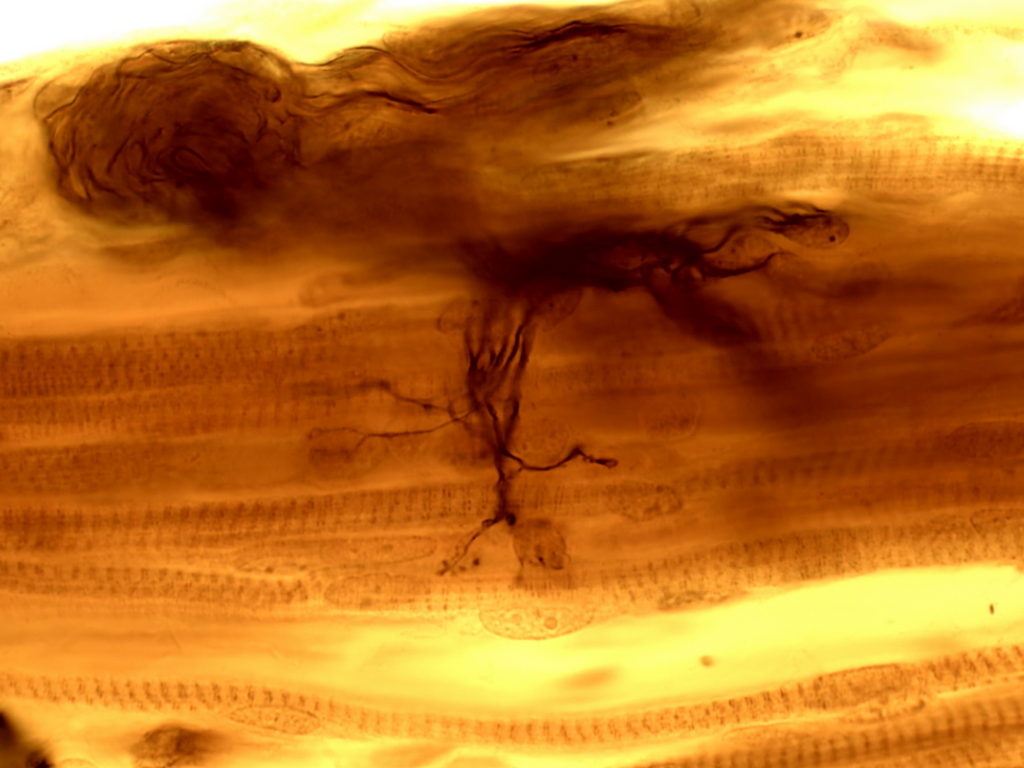

- Połączenie nerwowo-mięśniowe